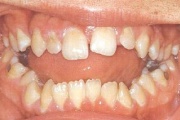

Vali sind huvitav pilt ja me näitame sellega seotud haigust ja sümptomeid